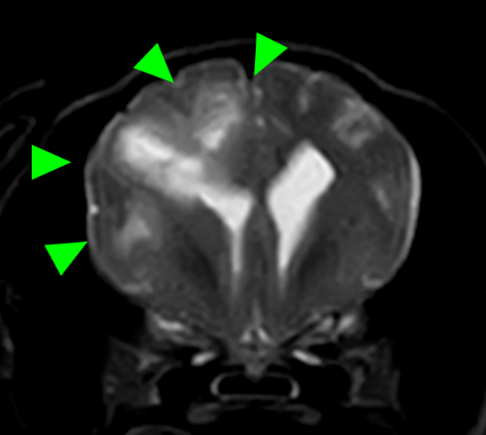

犬種 チワワ

年齢 7歳齢

体重 2.95kg

性別 去勢雄

運動失調(ふらつき、登れていた段差も登らなくなった)の主訴で来院。

初診から4か月後に重積発作で来院されたため、MRI検査を実施。

MRI検査:

右前頭葉にT2 強調画像/FLAIR 画像で高信号、T1 強調画像で一部低信号を示し、辺縁部で一部造影増強を示すびまん性の所見を認めた。この所見は、DWI 画像で高信号、ADC-map で大半が等~低信号を示していた。また左側前頭葉にも同様の信号所見を示す微小病変を認めた。

T2強調画像 水平断像